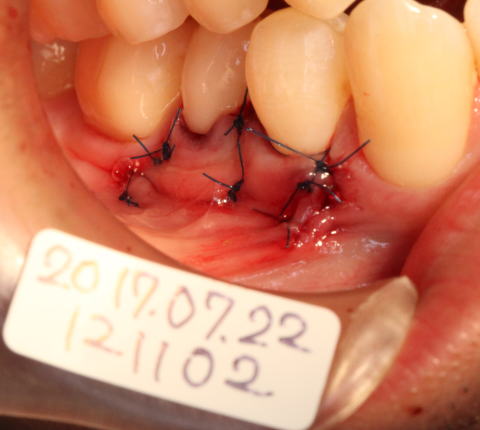

2017-07-22 骨が足りない所に骨補填剤等を充填して歯肉弁歯冠側移動術を行いました。 |

![]() |

2017-08-12 抜糸。予後良好。 しみととれていました。 46番は、オペ後、約4ヶ月後 44番、45番はオペ後、約3週間後 |